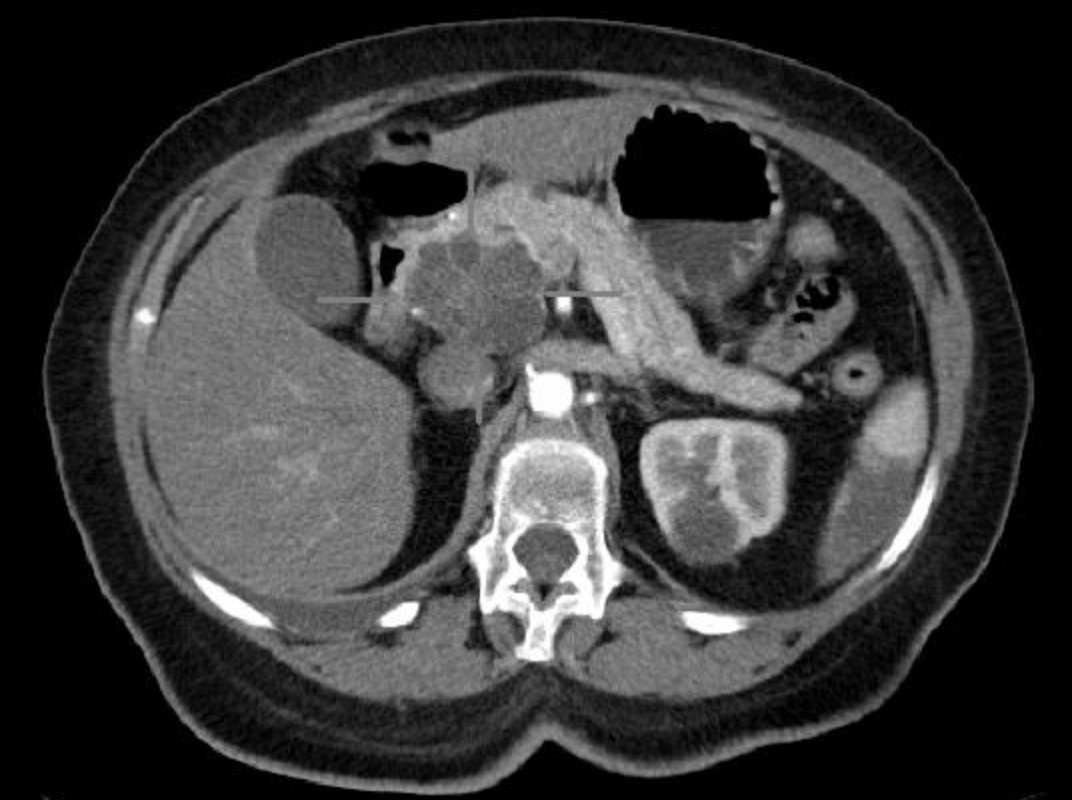

Майкл Уоллес (Michael Wallace), гастроентеролог клініки Майо в США, назвав ранній симптом особливо небезпечного раку підшлункової залози, який зазвичай розвивається непомітно. Про це повідомляється в прес-релізі на MedicalXpress. За словами фахівця, тривожною ознакою є цукровий діабет, який виявляється у людей з нормальнлю або низьклю вагою, а також у людей, які входять в групу високого ризику захворювання на рак, наприклад, у літніх або тих, хто вживає тютюн.

Крім того, останнім часом з’явилися нові методи ранньої діагностики і лікування раку підшлункової залози. За допомогою МРТ можна ідентифікувати заповнені рідиною кісти всередині органу, які підвищують ймовірність розвитку пухлини. Також можна взяти зразки травного соку, що виділяється залозою, або стулу, щоб виявити маркери раннього раку.

Тонкоголкова біопсія дозволяє взяти досить біологічного матеріалу у злоякісної тканини, щоб вивчити генетичні послідовності в пухлинних клітинах і визначити найкращі ліки, націлені на новоутворення, якщо інші методи вже не допомагають.